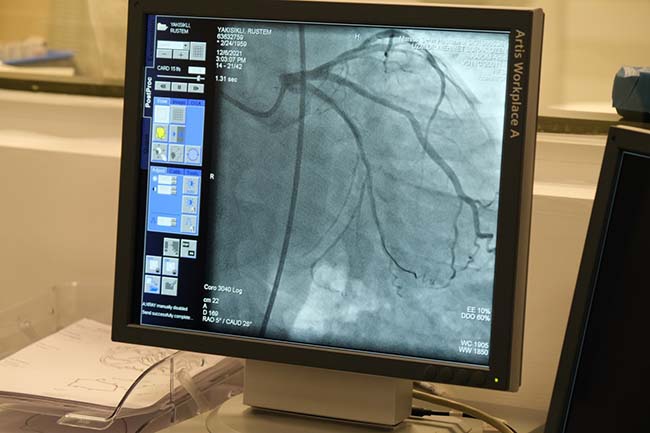

Halı sahalarda yaşanan ölümlerin tıp dilinde ani kardiyak ölüm olduğunu belirten Uzm. Dr. Özen, “Halı sahalarda gördüğümüz şey ani kalp durması. Bizim tıp dilinde de ani kardiyak ölüm. Bunlar hastane dışındaki ölümlerin en önemli nedenleri. Ani kardiyak ölümler her yaşta görülebiliyor. Bu ortalama olarak bizim elimizde net bir veri olmamasıyla beraber Türkiye'de en az 200 vatandaşımızı ani kardiyak ölümle kaybettiğimizi düşünüyoruz. Ani kardiyak ölüm özellikle kalp hastalığı olanlarda, ritim bozukluğu olanlarda, doğuştan kalp rahatsızlığı olanlarda daha sık görülüyor. Bu ani kardiyak ölümler erkeklerde 4 kat daha fazla görülüyor. Bu ani kardiyak ölümlerin yüzde 70'inin nedeni kalp damarının tıkanması. Fakat özellikle biz genç hastalarımızda bunu ritim bozukluğu şeklinde görüyoruz. Ölümcül ritim bozuklukları halı sahalarda genç hastalarda daha sık gördüğümüz neden. Ani kardiyak ölüm temel olarak bugün şikayeti olmayan hastanın sebepsiz olarak 1-2 saat içerisinde kaybedilmesi” dedi.

Toplum tarafından sıkça kullanılan alanlarda ani kardiyak ölümleri engelleyebilmek için yapılabilecekleri anlatan Dr. Özen, “Ani kardiyak ölümleri engellemek amacıyla sosyal olarak da yapılması gerekenler var. Biz bu hastaların çoğunu ritim bozukluklarından kaybediyoruz. İnsanların çok sık yaşadığı yerlerde ve ağır spor yapılan yerlerde, havaalanları, kamu binaları, halı saha ve spor yapılan diğer merkezlere ‘şok aleti' dediğimiz otomatik eksternal defibrilatör, bunlar bir paket şeklindedir, hastaya direkt bağlanır. Hastada ölümcül bir ritim bozukluğu varsa hastaya müdahale eder. En son yapılan İstanbul Havaalanı'nda bu eksternal defibrilatörlerden bulunuyor. Bunlar eğer yaygınlaşırsa, halı saha, sinema, alışveriş merkezlerinde, kamu binalarında eksternal defibrilatörlerden bulunursa biz bu nedenle kaybettiğimiz hasta sayısını azaltabiliriz” diye konuştu.